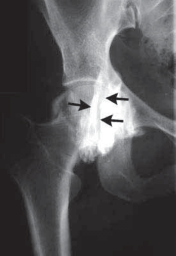

8. Iliopsoas bursography and ultrasonography may be helpful to rule in, but not rule out, the diagnosis (

FIG 3

).

FIG 3•

Iliopsoas bursography silhouettes the iliopsoas tendon (

arrows

) with contrast.

A.

In flexion, the iliopsoas tendon lies lateral to the femoral head.

B.

In extension, the iliopsoas tendon moves medial. (Courtesy

A B of J. W. Thomas Byrd, MD.)